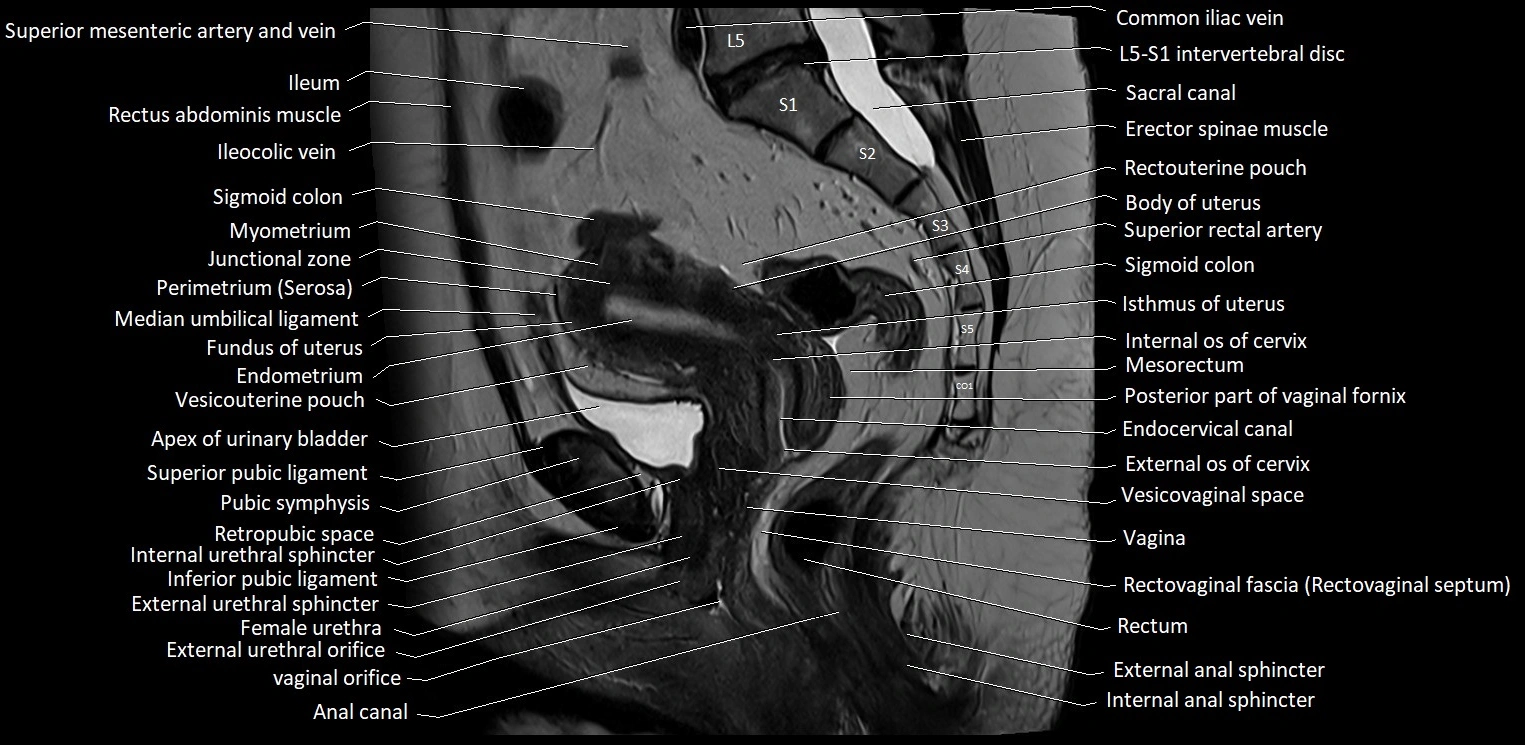

- Anal canal

- Apex of urinary bladder

- Body of uterus

- Coccyx

- Common iliac vein

- Endocervical canal

- Endometrium of uterus

- Erector spinae muscles

- External anal sphincter

- External iliac artery

- External iliac vein

- External os of the cervix

- External urethral orifice

- External urethral sphincter (female)

- Female urethra

- Fundus of uterus

- Ileum

- Inferior pubic ligament

- Internal anal sphincter

- Internal os of the cervix

- Isthmus of uterus

- Junctional zone of uterus

- L5–S1 Intervertebral disc

- Median umbilical ligament

- Mesorectal fascia

- Mesorectum

- Myometrium of uterus

- Perimetrium of uterus

- Posterior fornix of cervix

- Pubic symphysis

- Rectouterine pouch (pouch of Douglas)

- Rectovaginal septum (rectovaginal fascia)

- Rectum

- Retropubic space

- Sacral canal

- Sigmoid colon

- Superior pubic ligament

- Superior rectal artery

- Vagina

- Vesicouterine pouch

- Vesicovaginal space